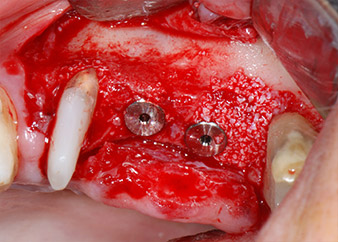

One month later, on the day of surgery, pain and inflammation at tooth 24 were minimal, but mobility of Miller class 2 was still present. After opening the flaps and cleaning the periapical and peri radicular infected tissue, the extent of the bone defect became obvious (Figs. 2 and 3).

At the buccal root, all vestibular and distal bone was missing. Attachment was essentially restricted to the palatal root, underlining the preliminary poor prognosis. Tooth 27 also showed a reduced horizontal attachment and a minimal apical rarefaction (cf. Fig. 1) without clinical symptoms.

total loss of bone and attachment

Fig. 2 and 3: After raising flaps, one month after endodontic revision and initiation of full-mouth periodontal therapy, the buccal root of tooth 24 showed a total loss of bone and attachment.

However, we maintained our initial plan to retain both teeth as temporary bridge abutments during the six-months osseointegration period of the implants. At reentry, the situation would have to be reassessed. First, in an attempt to manage the endo-perio problem, the remaining root surface was carefully debrided with piezoelectric equipment (Piezomed, W&H, used with the spatula-shaped insert S1, originally designed for erosion of the lateral sinus wall) (Fig. 4).